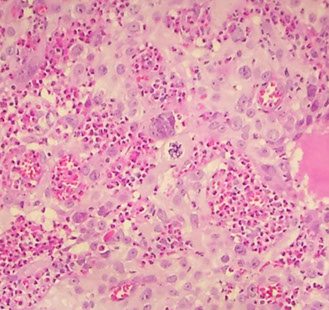

Follicular cervicitis

Assoc c chlamydia infx

- see tingible body macrophages in lymph nodes

Follicular cervicitis c macrophage inclusion, assoc c chlamydia infx